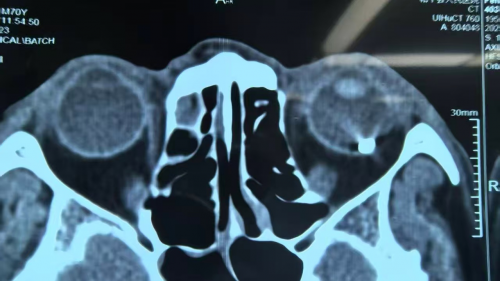

次日,彭叔左眼症状没有好转,便赶忙前往当地医院就诊。经过左眼CT检查,结果显示左眼球偏外侧存在高密度影,医生考虑有异物残留。但当地医院受限于医疗条件,无法对其进行有效医治,于是建议彭叔转至上级医院做进一步治疗。

18日,心急如焚的彭叔在儿子的陪伴下来到深圳华厦眼科医院,慕名寻求眼底病眼外伤专家赵铁英院长的帮助。此时,距离彭叔受伤已过去两天。时间紧迫,因为异物长时间留在眼内,极有可能引发感染,造成眼球不保等不可逆的严重后果。为了争分夺秒地进行救治,医院迅速启动了“急诊绿色通道”,优先安排彭叔进行相关检查,诊断为“左眼眼球穿通伤、左眼角膜穿通伤、左眼球内异物以及左眼外伤性白内障”。

图:彭叔术前CT片与术后眼内取出的异物